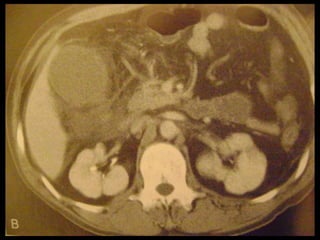

Achados na TC: cálculos biliares, espessamento da

parede, alterações inflamatórias

perivesiculares, bile com alta

atenuação, borramento da interface VB-fígado e

aumento transitório da atenuação do fígado

perivesicular;

Colecistite aguda US é a modalidade de imagem de escolha; Em geral, a TC é realizada para avaliar pacientes com suspeita de complicações do quadro de colecistite aguda, como perfuração por exemplo. Achados na TC: cálculos biliares, espessamento da parede, alterações inflamatórias perivesiculares, bile com alta atenuação, borramento da interface VB-fígado e aumento transitório da atenuação do fígado perivesicular;